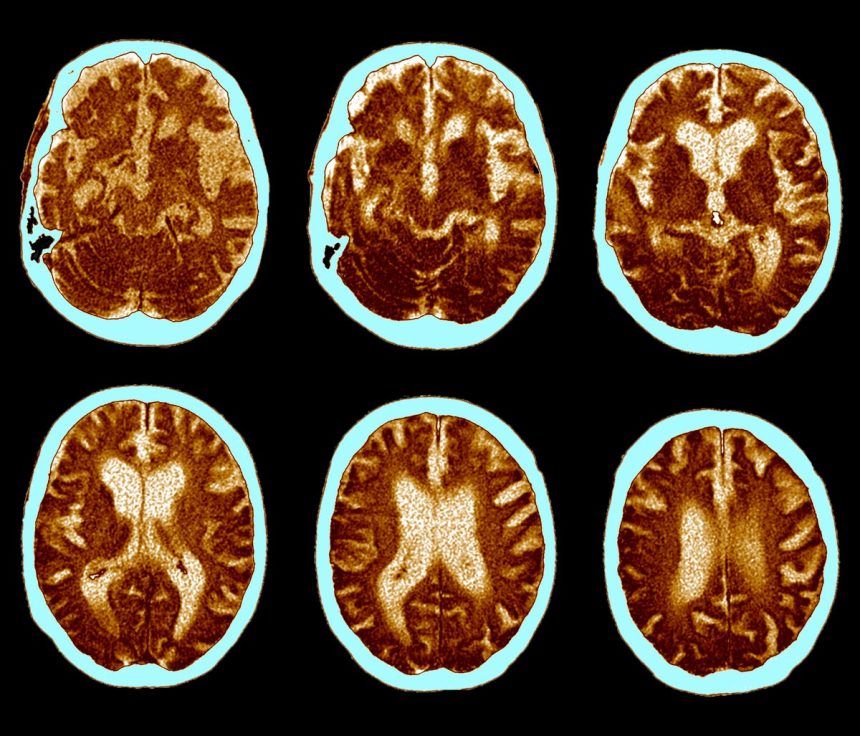

Drucker pointed out that the structure of semaglutide may have hindered its ability to penetrate certain regions of the brain crucial for memory and cognitive function, such as the hippocampus. He also suggested that differences in dosage or method of administration, as seen in injectable forms of GLP-1 drugs, could potentially yield different results. However, he cautioned that higher doses in older adults could carry additional risks.